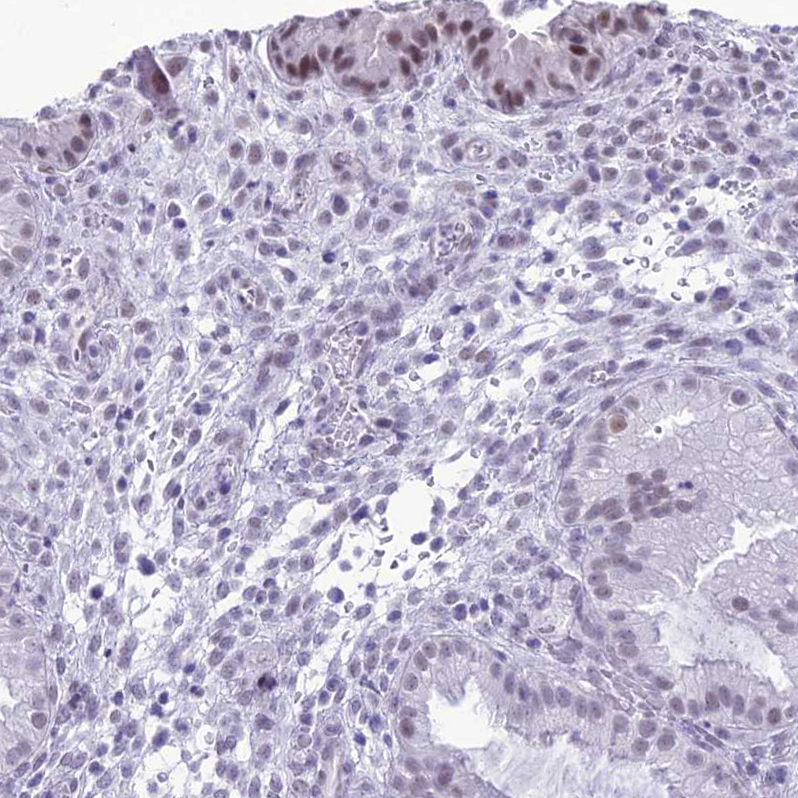

Immunohistochemical staining of human testis shows strong nuclear positivity in Leydig cells, as well as moderate positivity in cells in seminiferous tubules.